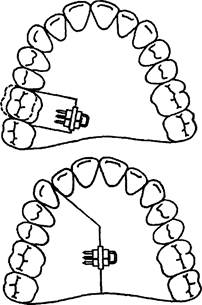

При равномерном сужении левой и правой половины зубного ряда целесообразно применять расширяющую пластинку с расположением винта на уровне срединного небного шва (рис. 13.36). При необходимости перемещения одного зуба или группы зубов в трансверсаль-ном направлении изготавливают пластину с секторальным распилом на верхнюю челюсть (рис. 13.37). При более значительном сужении переднего участка зубного ряда следует использовать расширяющую пластинку с петлей для ограничения расширения боковых участков зубного ряда (рис. 13.38).

Ортодонтический винт может быть использован при перемещении зубов по сагиттали. Так, при небном положении верхних передних зубов применяют пластинку с секторальным распилом на верхнюю челюсть. При этом создают место для аномально расположенных клыков (рис. 13.39).

В случае вестибулярного положения клыка, причиной которого явилось мезиальное перемещение боковых зубов, можно изготовить ортодонтический аппарат для их дистального перемещения (рис. 13.40).

Рис. 13.37. Пластинка на верхнюю челюсть с секторальным распилом для перемещения одного зуба или группы зубов.

Рис. 13.40. Пластинка на верхнюю челюсть с секторальным распилом для дистального перемещения верхних боковых зубов.